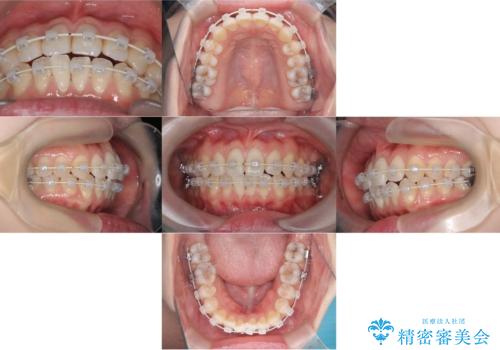

【ワイヤー矯正】前歯の突出感、下の歯の並びを良くしたい

- 主訴:上の前歯の突出感と下の歯の並びを改善したい

非抜歯で矯正治療を行った場合と、上下左右4番目の歯を抜歯して矯正治療を行った場合のシミュレーションを見ていただき、非抜歯での矯正治療を希望されました。

非抜歯にて矯正治療を行いました。

IPRを行い、前歯部の突出感の改善に努めました。

期間:1年9カ月